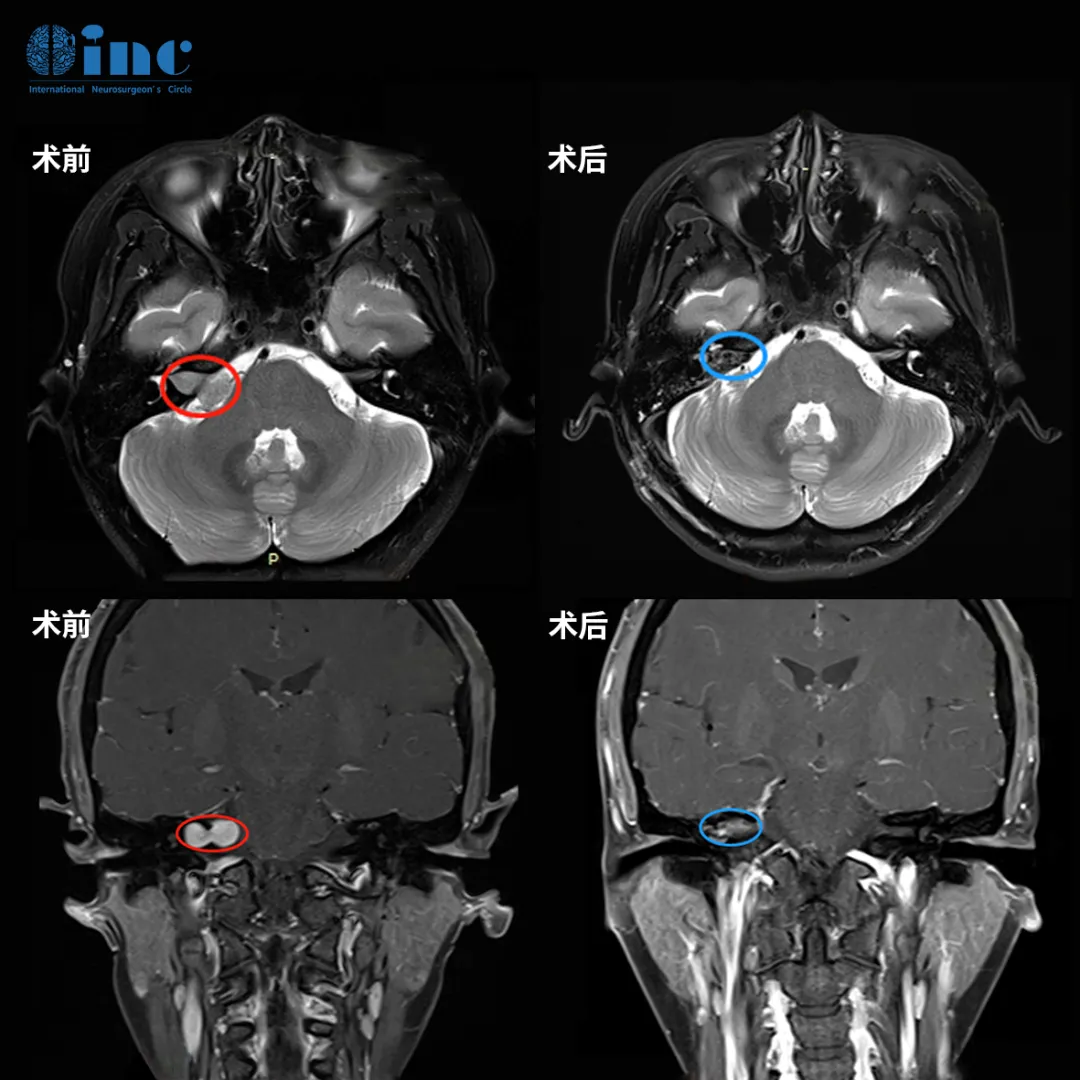

她找到INC巴教授为她主刀,结果令人欣慰:肿瘤不仅被完全切除,面神经也成功保留,她没有面瘫。

结果令人欣慰:肿瘤被完全切除,面神经也成功保留。姜女士醒来后第一件事就是确认自己的面部功能,当发现一切正常时,她心中的巨石终于落地。